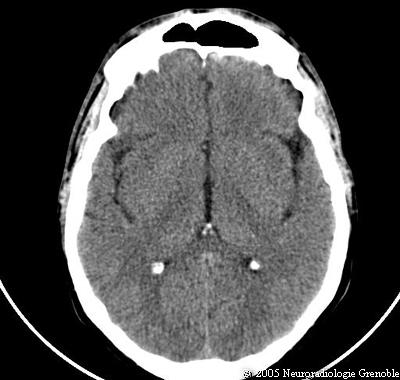

Radioanatomie TDM de l'encéphale

TDM cérébrale sans injection